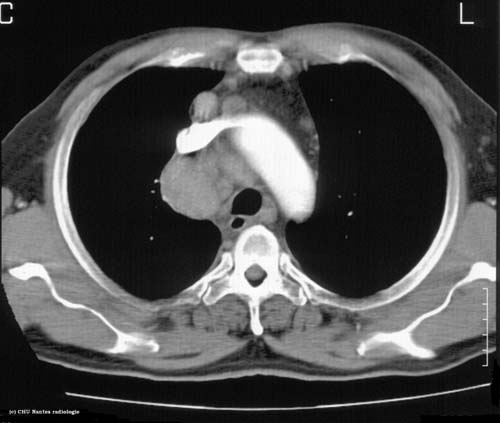

Syndrome médiastinal

TDM